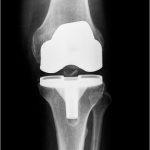

Η αρθροπλαστική γόνατος είναι μία χειρουργική επέμβαση με την οποία ένα προσβεβλημένο γόνατο από οστεοαρθρίτιδα ή άλλες εκφυλιστικές βλάβες αντικαθίσταται από μία ειδικά σχεδιασμένη πρόθεση.

Μία απλή ακτινογραφία επιβεβαιώνει την διάγνωση και την έκταση της βλάβης.

Η επιλογή της πρόθεσης, της χειρουργικής τεχνικής εξαρτάται από την ηλικία, το σωματικό βάρος, τις δραστηριότητες και την γενική κατάσταση της υγείας του ασθενή.